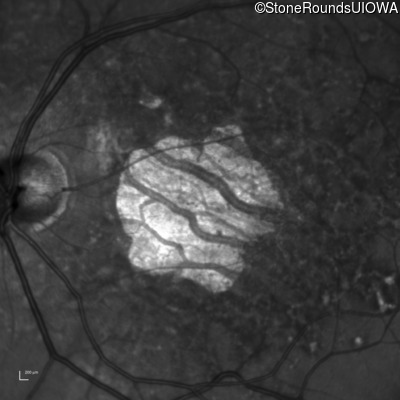

Infrared Fundus Photograph - Left - 20/125

Exemplar